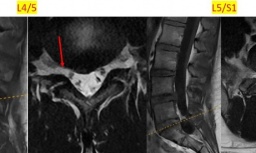

Tại Khoa Chấn thương chỉnh hình và Y học thể thao, Bệnh viện Đại học Y Dược, Đại học Quốc gia Hà Nội cơ sở Linh Đàm, các bác sỹ ghi nhận một bệnh cảnh phức tạp. Khớp gối trái của bệnh nhân biến dạng rõ rệt, mất hoàn toàn chức năng gấp duỗi. Kết quả chụp cộng hưởng từ cho thấy tổn thương nặng với rách bán phần dây chằng chéo trước, dây chằng chéo sau và rách sụn chêm ngoài.

TS.Nguyễn Huy Phương, Trưởng khoa Chấn thương chỉnh hình và Y học thể thao cho biết, đáng lo ngại nhất là sự lắng đọng dày đặc của các tinh thể urat trong khớp. Những tinh thể này bám chắc như rễ cây, gây viêm dày màng hoạt dịch và dẫn tới tình trạng kẹt khớp cơ học. Nếu không được can thiệp kịp thời, nguy cơ hủy hoại sụn khớp vĩnh viễn là rất cao.

Sau khi hội chẩn liên chuyên khoa, các bác sỹ quyết định thực hiện phẫu thuật nội soi khớp gối. Dưới hệ thống nội soi độ phân giải cao, hình ảnh các tinh thể urat trắng đục, sắc nhọn như thạch nhũ xuất hiện dày đặc, xâm lấn gần như toàn bộ khoang khớp.

Thông qua các đường rạch nhỏ khoảng 1 cm, ê kíp phẫu thuật tiếp cận toàn bộ khoang khớp. Hình ảnh nội soi cho thấy các tinh thể urat lắng đọng với mật độ dày, xâm lấn nhiều cấu trúc quan trọng trong khớp.